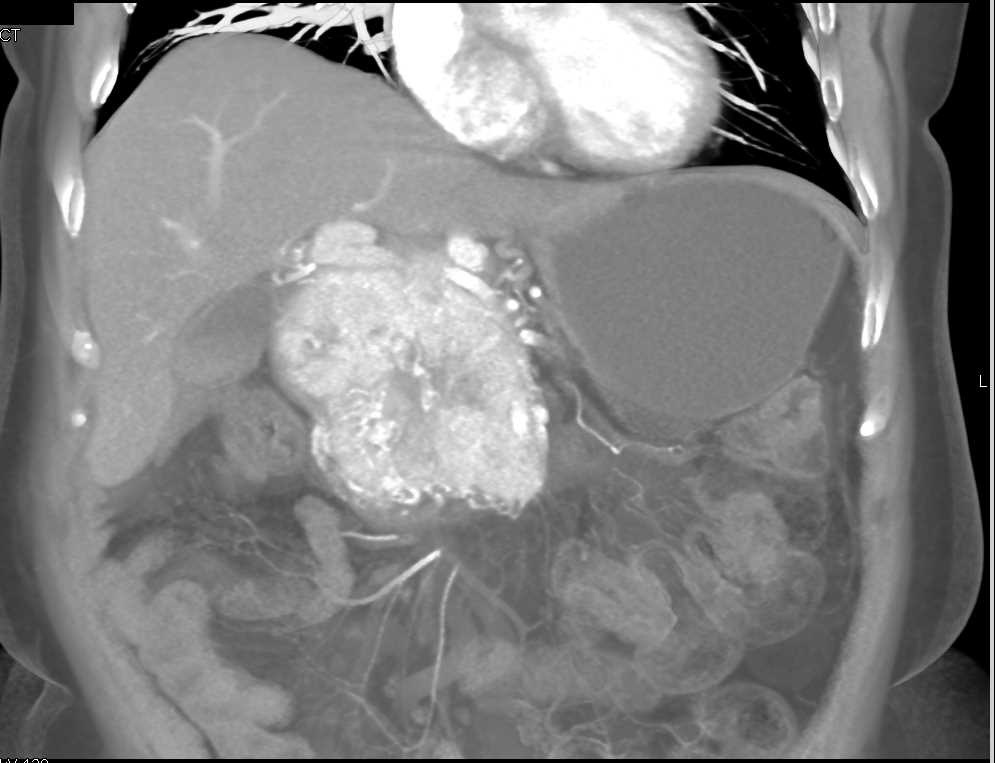

Neuroendocrine Tumor Pancreas